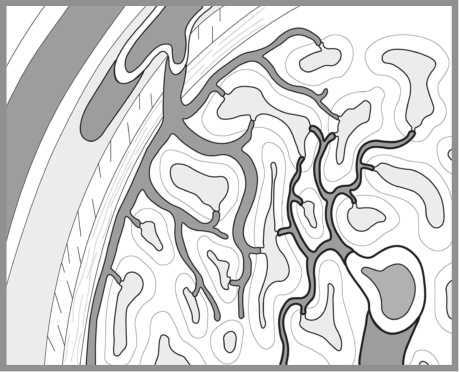

![]() Рис. 5. «Соитие». Рисунок из дневников Леонардо да Винчи (1475–1518 гг.) В одном из рисунков, содержащихся в известных «Дневниках» Леонардо, — «Фигура соития» — изображен срез гениталий мужчины и женщины во время полового акта стоя. Рисунок отражает его понимание, что член входит во влагалище, как ключ в замочную скважину. Он писал: «Женщине нравится, чтобы пенис был как можно крупнее, тогда как мужчина желает от женского чрева обратного». Недавние рентгенологические исследования с трехмерной реконструкцией изображения позволили уточнить анатомические соотношения гениталий в процессе полового акта; эти данные во многом подтвердили представления Леонардо до Винчи. Статья «Магнитно-резонансное изображение мужских и женских гениталий в процессе соития»11 получила в 2000 году Шнобелевскую (антинобелевскую) премию, что свидетельствует как минимум о проявлении интереса к данному исследованию. ![]() Рис. 5 а. МРТ гениталий в процессе полового акта. В период, когда Леонардо занимался изучением строения человеческого тела, в средневековой Европе господствовали медицинские взгляды греческого ученого Галена (131–217). Он считал, что всем человеческим телом управляет «внутреннее тепло» (воздух). Оно же поступает в пенис и вызывает эрекцию. Еще до систематических анатомических исследований, начавшихся с 1503 года, Леонардо присутствовал на публичной казни через повешение и затем вскрытии трупов этих преступников. Он пишет: «Я видел мертвецов с эрегированным членом, что часто происходит у тех, кого казнят повешением. Их пенисы были очень плотны и тверды и наполнены большим количеством крови». Догадка о возникновении эрекции в результате интенсивного притока крови была подтверждена Леонардо да Винчи дальнейшими исследованиями. Амбруаз Паре, которого считают отцом современной хирургии, опубликовал в 1585 году научную работу, содержащую аналогичный вывод. Вероятно, ему не было известно, что на 100 лет раньше это открытие сделал не медик, а великий художник. Однажды бельгийский врач Андреас Везалий (1514–1564), прогуливаясь ночью за городской стеной, набрел на труп повешенного преступника и отрезал у него руку и половой член. Исследовав их, он сделал ошеломляющий вывод: многое из написанного Галеном о теле человека не соответствует действительности. В 1543 году Везалий опубликовал свой труд «О строении человеческого тела» объемом 663 страницы (28 см в ширину, 42 в высоту, в переплете из пурпурного бархата). Как писал Везалий: «В отношении полового члена истина заключается в том, что при акте зачатия этому органу дана такая сила наслаждения, что и молодые, и старые мужчины ощущают потребность размножаться». Анатом и физиолог голландского происхождения Ренье де Грааф завершил к 1668 году самое детальное на тот период исследование строения полового члена. Он использовал свою методику достижения стойкой эрекции членов трупов и значительно превзошел предшественников в понимании ее механизмов. Им доказана не только важная роль интенсивного притока крови к пенису, но и ее стойкого удержания. Гипотеза, что это происходит за счет сжатия мышц, окружающих кавернозные тела, оказалась неверной. Вскоре после опубликования своего труда «Трактат относительно генеративных органов мужчины» он в 1673 году умер, занимаясь лечением больных чумой. Ему было 32 года… Еще один шаг к пониманию строения и функционирования полового члена сделал голландец Фредерик Рюйш (1638–1731). Используя специальный состав жидкости и шприцы, он изготавливал препараты частей тела, словно отлитые из воска. При этом в пенисе были четко различимы артерии и вены. Его модели органов не только были объектом изучения, но также составили коллекции, в которых основными экспонатами служили половые члены. Они были раскуплены европейскими монархами, включая царя Петра I. ![]() Рис. 6а. Кавернозная ткань во время расслабления пениса. ![]() Рис. 6б. Кавернозная ткань во время эрекции пениса. Чтобы закрасить оставшиеся белые пятна в истории познания строения и эрекции полового члена, опишем последние крупнейшие открытия в этой области. В самом начале XXI столетия к урологам пришло понимание, что именно за счет расслабления гладкой мускулатуры, которая входит в состав мельчайших артерий (артериол) и ячеек (синусоидов), кавернозная ткань способна принять и удерживать достаточное количество крови для создания ригидности (твердости) полового члена. При быстром расслаблении этой гладкой мускулатуры артериолы расширяются, сопротивление поступающему потоку крови резко падает, а увеличившаяся в объеме кавернозная ткань прижимает к белочной оболочке и сдавливает вены, по которым кровь могла бы утекать (окклюзия вен). Притекающая кровь оказывается как бы в ловушке, давление в кавернозных телах резко нарастает и становится выше артериального систолического. Однако трофика (питание) тканей члена не нарушается, так как минимальный уровень притока и оттока крови сохраняется. Эти предварительные сведения и выводы были подтверждены последующим изучением анатомии пениса с использованием сканирующей электронной микроскопии. Оставалось неясным, что представляет собой вещество, вызывающее расслабление гладкой мускулатуры кавернозной ткани и расширение ее сосудов и синусоидов. Эту загадку независимо друг от друга разгадали трое ученых: Роберт Фарчготт, Луис Игнарро и Ферид Мурад. Им удалось доказать, что молекула оксида азота (NO), вырабатываемая эндотелием сосудов, и является тем самым веществом, которое вызывает расширение всех периферических (мельчайших) артерий. Основные научные исследования относятся к 1992 году. Позднее авторы стали лауреатами Нобелевской премии (1998) за работу «Монооксид азота как сигнальная молекула в сердечно-сосудистой системе». Все сосудистые реакции, осуществляющие эрекцию, контролируются нервной системой. Ее активное участие в этом процессе впервые установил в 1863 году немецкий ученый Конрад Экхард. Он обнаружил напряжение члена собаки при воздействии на тазовые нервы электрическим током. |